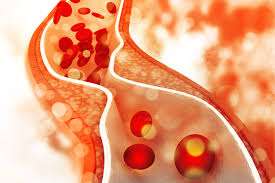

La enfermedad cerebrovascular oclusiva, también conocida como accidente cerebrovascular isquémico, es una condición patológica caracterizada por una interrupción en el flujo sanguíneo hacia una región del cerebro, lo que resulta…